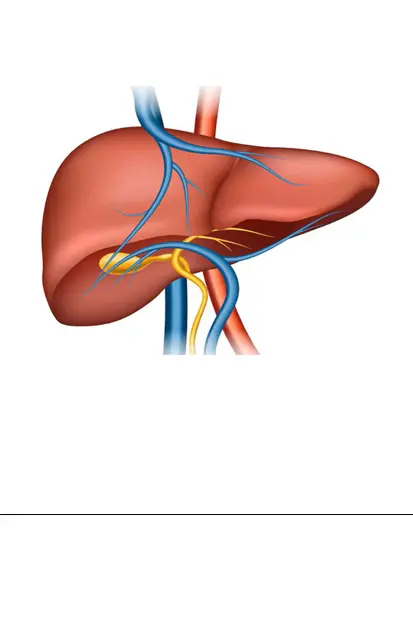

Achieving this ambition is crucial. If left untreated, hepatitis C can lead to life-threatening conditions like liver cancer or liver failure. While significant progress is being made to reduce the number of people with hepatitis C, more needs to be done to prevent new infections and reinfections.